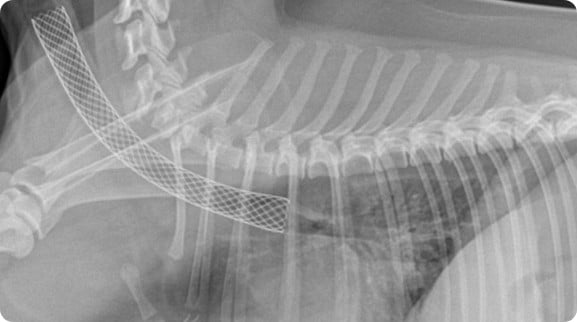

시그니처동물의료센터 『중재시술 센터』에서는 기관 스텐트를 비롯한 동물 중재술을 특화 진료 분야로 두고 있습니다. 본원 의료진은 영국의 INFINITI Medical 사에서 실시하는 기관 스텐트 장착 트레이닝을 이수하였으며, 국내에서 기관 허탈이 많이 발생하는 품종과 체형, 체중을 고려한 대부분의 환자에게 즉시 적용할 수 있는 다양한 동물 전용 기관 스텐트를 다수 확보해 응급 상황에서도 정확하고 안전하게 기관 스텐트 장착이 가능하도록 노력하고 있습니다. 최근에는 국내 스텐트 제조회사와 동물 전용 기관 스텐트를 협력 제조하여 필요한 환자에게 이를 적용하고 있습니다. 영상 센터와의 협진으로 정확하고 국내 최다 케이스를 보유한 경험으로 각 환자에게 적합한 치료로 가장 나은 치료 결과를 위해 노력합니다.